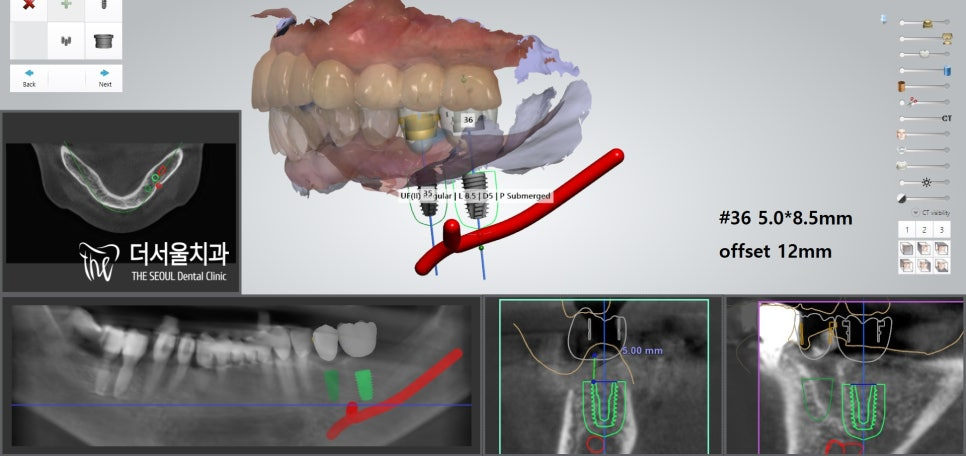

디지털 분석을 사용하여

골질과 골양, 인접치와의 거리,

대합치와의 교합 관계를 파악하여

픽스처의 직경과 폭,

그리고 식립 위치를 정했습니다.

이후 미리 계산된 위치에 맞춰

아랫니 임플란트 과정을 진행했습니다.